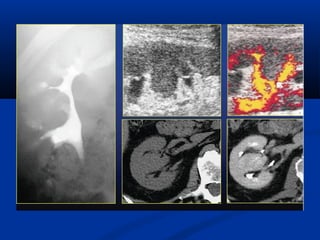

Khieám khuyeát noái lieàn chuû moâKhieám khuyeát noái lieàn chuû moâ

Bieán theå bìnhthöôøngBieán theå bình thöôøng Khieám khuyeát noái lieàn chuû moâKhieám khuyeát noái lieàn chuû moâ

Khieám khuyeát noáilieàn chuû moâKhieám khuyeát noái lieàn chuû moâ